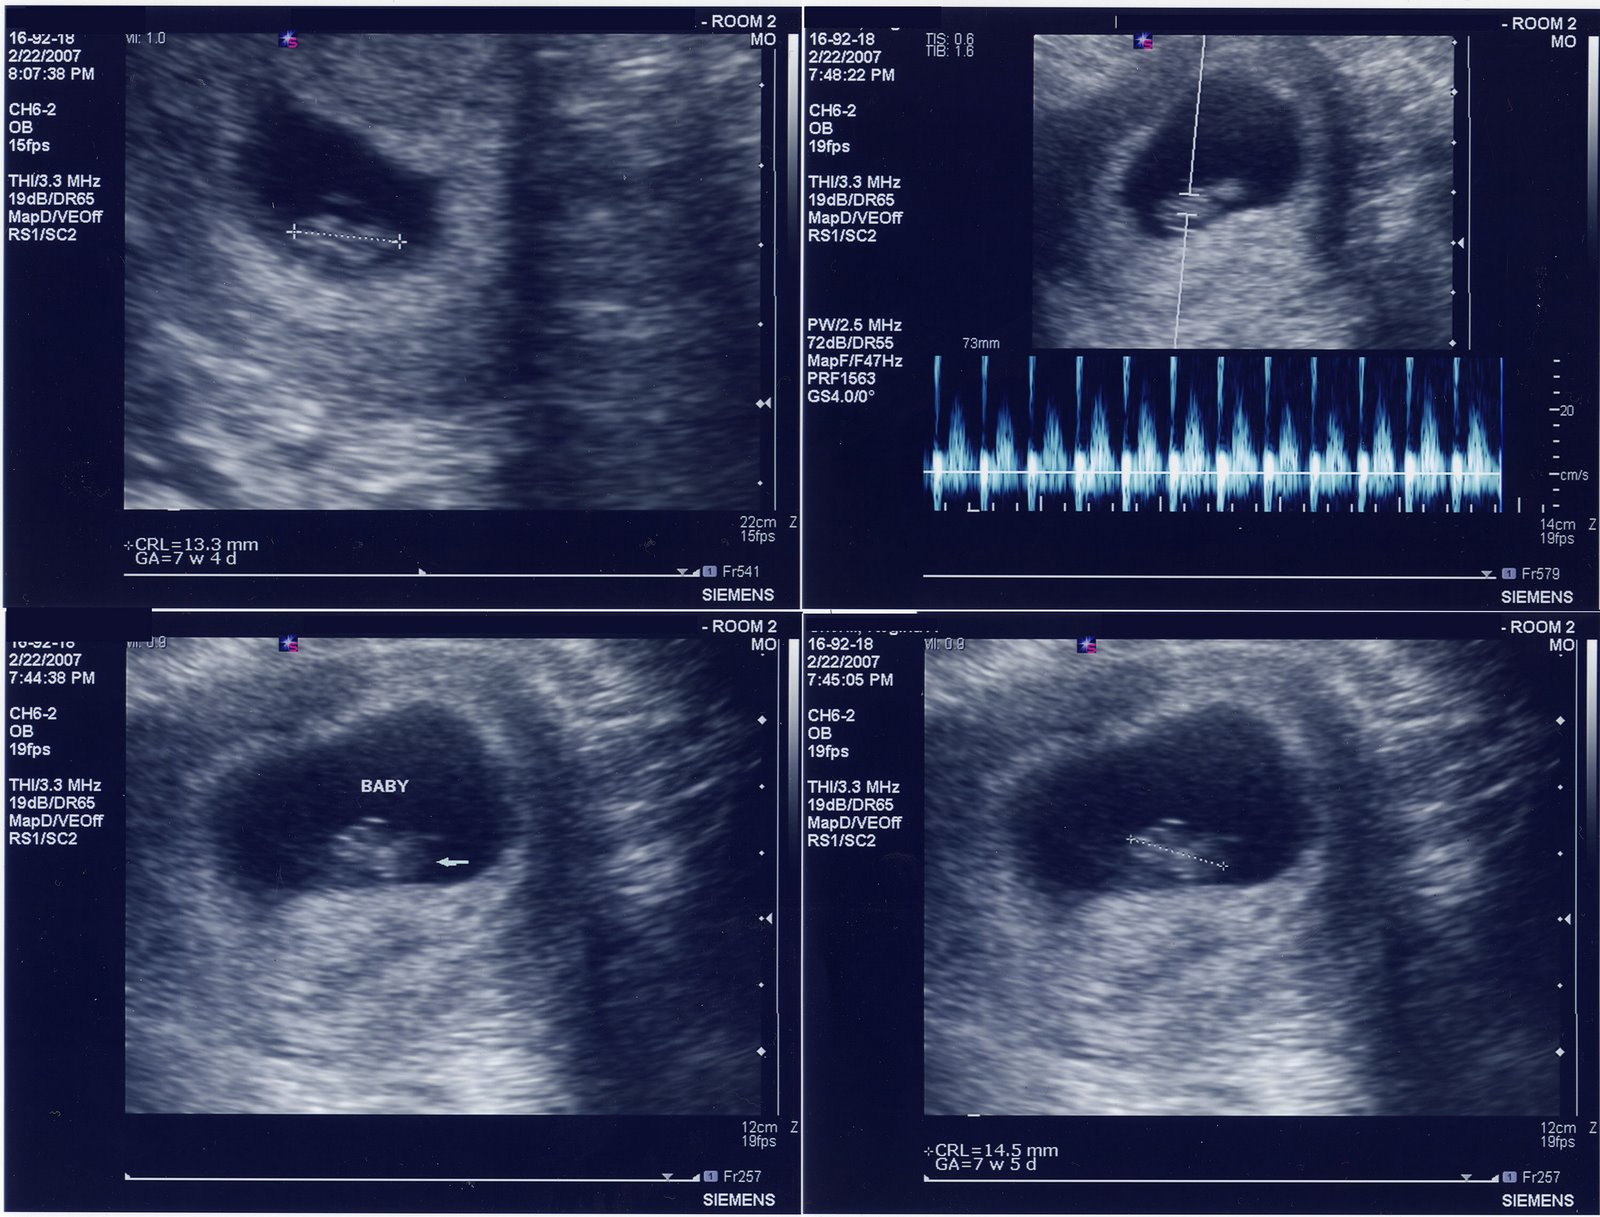

Well, sort of! I can’t believe it’s been a year since we found out we were pregnant. I think Claire’s changed quite a bit since then and she’s certainly more photogenic. So here’s a blast from the past – one of our first ultrasound images where Claire (then known as “bean”) measured a whopping 13 mm (half an inch).

These are the ultrasound images we used to surprise the Grealis and Seamon clans with our news. We wrapped them up with a ribbon and put them on dinner plates.